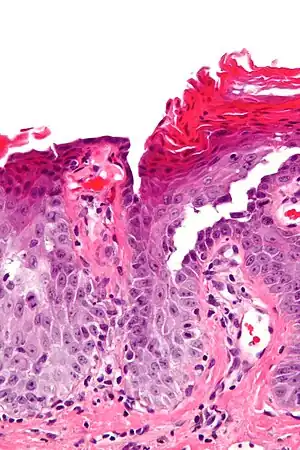

Micrograph of transient acantholytic dermatosis, showing subcorneal separation and acantholysis. H&E stain.

It is characterized histologically by acantholysis,[3] with or without dyskeratosis.[4] Once confirmed, most cases of Grover's disease last six to twelve months, which is why it was originally called "transient". However it may last much longer. Nevertheless, it is not to be confused with relapsing linear acantholytic dermatosis.

Grover's may be suspected by its appearance, but since it has such a characteristic appearance under the microscope a shave skin or punch biopsy is often performed.